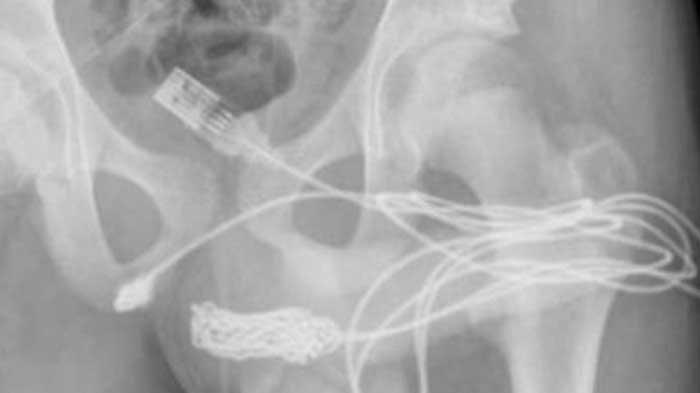

Karena mengalami kesakitan, remaja ini dibawa ke Rumah Sakit Universitas London dan menjalani pemeriksaan melalui x-Ray, sebelum ada keputusan bahwa kelaminnya akan dibedah.

Dokter bedah juga memotong sebagian otot bulbospongiosus yakni otot pada bagian kelamin manusia.

Setelah bagian tersulit tersebut berhasil dibedah, kabel USB yang tersangkut akhirnya bisa dikeluarkan.